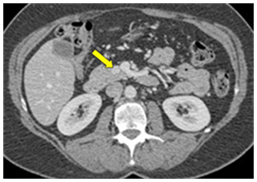

CT scan has many advantages since it can be easily performed, is non-invasive and the images are easily interpretable for the surgeon. Insulinoma typically appear as well-defined, rounded, homogeneously masses of the pancreas. Because the majority of insulinoma are usually smaller than 2cm, dynamic CT scan should be performed; the sensitivity of the dynamic CT scan in the detection of insulinoma ranges from 30% to 66%. Dual-phase contrast spiral CT scan is more sensitive than other noninvasive imaging studies. In a group of seven patients with tumors that were biochemically proven but not previously located by ultrasonography, CT scan, or magnetic resonance imaging, six of seven tumors ranging from 6 to 18 mm were detected by dual-phase spiral CT scan. Atypical CT scan imaging of insulinoma includes hypoattenuating masses on enhanced CT or intra-arterial dynamic CT, cystic masses, and calcified masses (Figure 1–3).26–30

Figure 1 Insulinoma in an 87-year-old man with intractable hypoglycemia. Dual phase CT scan through the pancreas demonstrates a subtle, well-defined 1-cm enhancing lesion (arrow) in the pancreatic neck. A small cyst is also seen. A well-differentiated 1.2-cm ICT was completely excised at surgery. Histologic stains were positive for insulin. The hypoglycemia resolved after surgery. 23